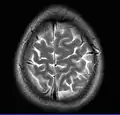

MRI of Brain

Cross-sectional T1-weighted MRI of a healthy human brain acquired with an ultra high-field MR of 7 Tesla field strength

Magnetic resonance imaging of the brain uses magnetic resonance imaging (MRI) to produce high quality two-dimensional or three-dimensional images of the brain and brainstem as well as the cerebellum without the use of ionizing radiation (X-rays) or radioactive tracers.

This axial T2-weighted (CSF white) MR scan shows a normal brain at the level of the lateral ventricles.